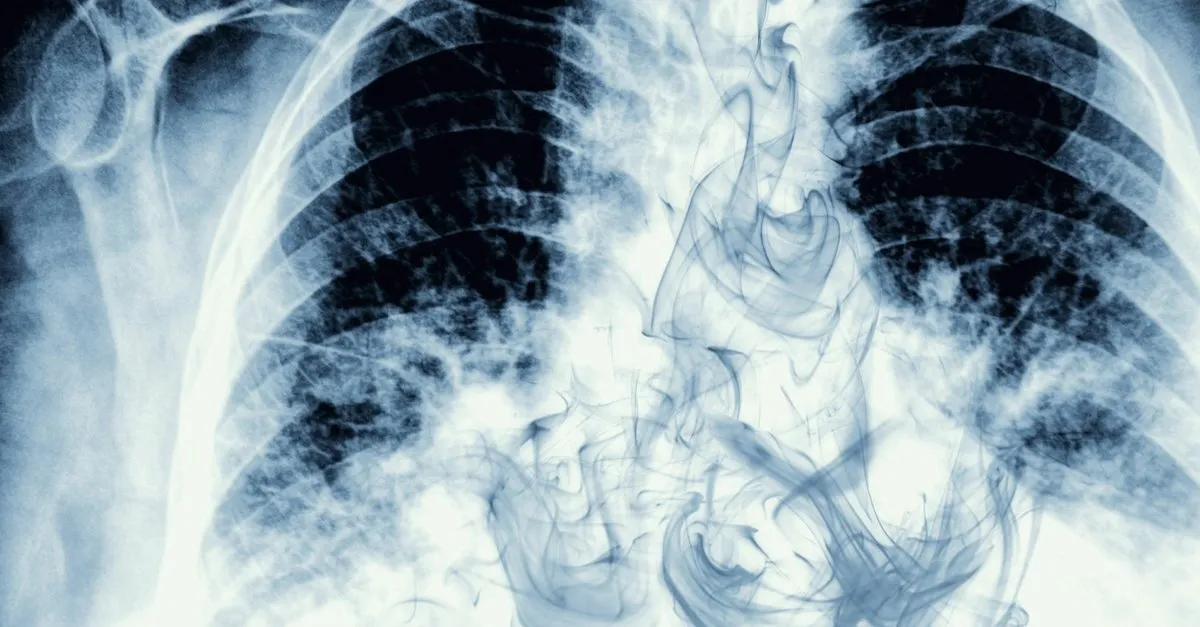

Yapısal olarak normal akciğer dokusundan olan hücrelerin ihtiyaç ve kontrol dışı çoğalarak akciğer içinde bir kitle tümör oluşturmasıyla başlar. Bu organda oluşan tümör yerleştiği yerde büyür ve sonrasında diğer organlara da sirayet ederek geniş bir bölgede yayılım gösterir. S onuç olarak akciğer kanseri erken evrelerde tespit edilemeyip son devrelerde ortaya çıkması sonucunda hasta nefes alıp vermekte zorlanmakta ve sancılı bir durum yaşamaktadır.

Akciğer kanseri nasıl olur belirtileri. Akciğer kanserinde ölüm belirtileri olarak artık hastalık farklı komplikasyon oluşur. Kontrolsüz şekilde çoğalan bu doku ve hücreler yayılarak çevredeki dokulara zarar verebilir gerekli önlemler alınmadığı takdirde metastaz ile sonuçlanan daha büyük sağlık sorunlarına yol açabilir. Yapısal olarak normal akciğer dokusundan olan hücrelerin ihtiyaç ve kontrol dışı çoğalarak akciğer içinde bir kitle tümör oluşturmasıyla başlıyor.

Burada oluşan kitle öncelikle bulunduğu ortamda büyüyor daha ileri aşamalarda ise çevre dokulara veya dolaşım yoluyla uzak organlara karaciğer kemik beyin vb yayılarak hasara yol açıyor. Akciğer kanserinin tedavisi olarak ise şunlar yapılmaktadır. Akciğer kanseri tanısı nasıl konur. Nefes darlığı balgam öksürük göğüs ağrısı sırt ağrısı oksijen makinesine bağlanması taşikardi akciğerde su toplanması böbrek yetmezliği oluşur.